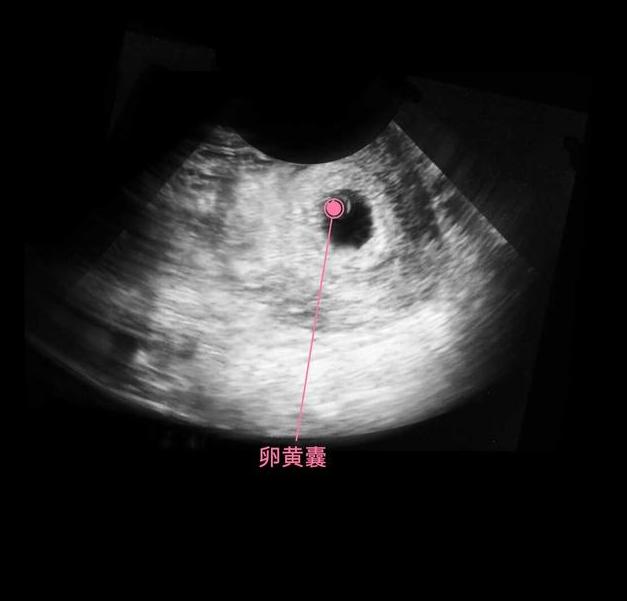

细胞继续分化,有的分化成胎儿的大脑,有的分化成胎儿的肾脏和肝脏,还有的分化成心脏等,这个时期的宝宝叫做胎芽,依靠着卵黄囊提供的营养,还用不到母体的营养呢,所以此时有了怀孕反应,没有食欲也没有关系,对胎儿发育的影响不大。

此时进入了第6周,胚胎已经具备了雏形,依稀可以卡到一个小人的形状,胚胎上下两面开始长出幼芽,将来发育成胎儿的手臂和小腿,面部器官开始形成雏形,不再是小海马的样子了。